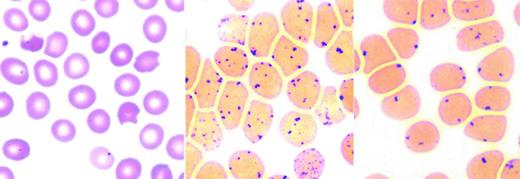

Altered hemoglobin stability leads to its denaturation with the production of hemichromes and formation of Heinz bodies. Hemichromes bind to the membrane and decrease erythrocyte deformability, leading to splenic trapping and shortening erythrocyte lifespan.2,3 Oxidative damage from free heme iron may further compromise the membrane. Common in unstable hemoglobinopathies, but also found in some enzymopathies and thalassemia, Heinz bodies are intracellular precipitates seen after supravital staining as dark globular aggregates. Splenic pitting of Heinz body-containing erythrocytes is the process in which a section of the membrane and the Heinz body inclusion is removed from the erythrocyte during its passage through splenic sinusoids, forming a “bite” or “blister” cell (Figure 1). Erythrocyte membrane loss eventually leads to removal from circulation.4

Unstable hemoglobins: peripheral blood smear and Heinz body preparation. Peripheral smear (left) shows “bite” cells with pitted-out semicircular areas of the red blood cell membrane as a result of removal of Heinz bodies by macrophages in the spleen. The Heinz body preparation (middle) shows increased Heinz bodies in the same specimen compared with a control (right). Reproduced with permission from Benz and Ebert.41

Detection of Heinz bodies requires preincubation of erythrocytes with a supravital stain such as methylene blue. Heinz bodies are single or multiple small, <2μ inclusions, frequently associated with the erythrocyte membrane, (Figure 1) best detected after 24-48 hour incubation in the absence of glucose. Heinz bodies are easier to detect postsplenectomy and are rarely detected in infants <6 months of age. Because Heinz bodies are detected in unstable hemoglobinopathy, beta-thalassemia, and enzymopathies, their best use is as a screening test.